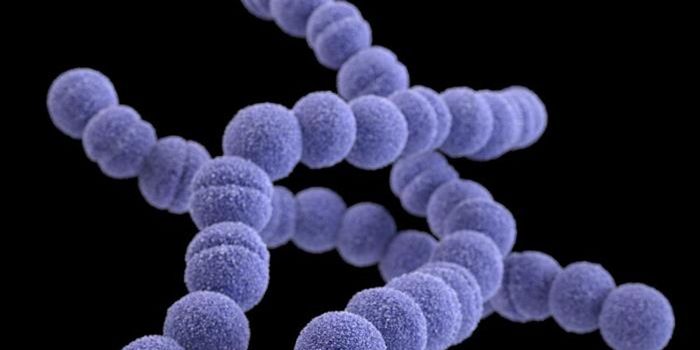

OCT 12, 2016ImmunologyThe key ingredient in the recipe that make staphylococcus and streptococcus infections so dangerous? Superantigen toxins ...